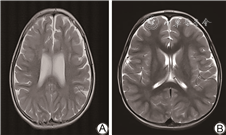

电话回访112例未同意复筛的患儿,其中拒接电话22例,接受电话回访的新生儿家长均回复婴儿生后至今(随访年龄0~3岁)健康。对8例确诊IEM患儿进行追踪随访及智力评估(随访年龄0~3岁),1例甲基丙二酸血症患儿早期头颅MRI显示双侧苍白球区、双侧尾状核头对称片状异常信号;1例戊二酸血症患儿早期头颅MRI提示额叶白质内等T1长T2信号,提示双侧额叶白质脱髓鞘。所有确诊病例均给予对应的治疗,包括特殊奶粉、补充左卡尼汀、维生素B12及尼替西农等,目前均生长发育良好。其中甲基丙二酸血症患儿随访至2岁、戊二酸血症患儿随访至2.5岁时头颅MRI均提示正常,智力正常。见图1、2。

本研究确诊甲基丙二酸血症1例,串联质谱筛查提示甲基丙二酸及丙酰肉碱明显增高,基因检测MUT基因c.729_730insTT(p.Asp244LeufsTer39)及c.424A>G(p.Thr142Ala)复合杂合变异,可能影响底物结合区和钴胺素结合区功能[10, 11],为致病变异。头颅MRI提示双侧额叶白质脱髓鞘,侧脑室轻度扩张,经维生素B12、左卡尼汀治疗,并予以饮食干预,临床症状消失,随访至2岁,韦氏量表测试智力正常,复查MRI正常。本研究确诊戊二酸血症Ⅰ型1例,该病可能导致大头畸形、肌张力异常及运动障碍等神经系统发育异常[12],该患儿血串联质谱提示戊二酰肉碱、戊二酰肉碱/辛酰肉碱水平升高,头颅MRI提示双侧颞部蛛网膜下腔明显扩大,基因检测及家系验证为GCDH基因c.1109T>C(p.L370P)及c.395G>A(p.R132Q)复合杂合变异,变异位点分别来源于父母,予口服维生素B2及左卡尼汀,随访到2岁半,复查头颅MRI正常,头围稍大,无神经系统发育障碍。